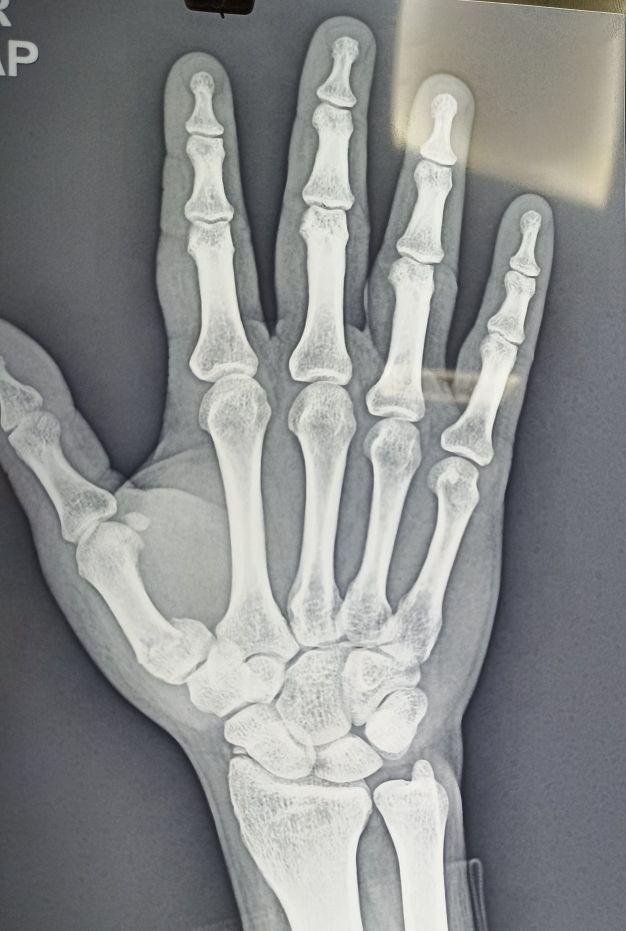

K Wire Procedure . K wire (kirschner wire) is passed through the skin then transversely through the bone and out the other side of the limb. K wire fixation of hand fractures. The wire is then attached to some form of traction so that the pull is applied directly to bone. Introduced in 1909 by martin kirschner, the. They can be placed percutaneously (through the skin) or can be buried beneath the skin. Each method has its advantages and disadvantages. These wires can be drilled through the bone to hold the fragments in place.

These wires can be drilled through the bone to hold the fragments in place. Introduced in 1909 by martin kirschner, the. They can be placed percutaneously (through the skin) or can be buried beneath the skin. K wire fixation of hand fractures. K wire (kirschner wire) is passed through the skin then transversely through the bone and out the other side of the limb. Each method has its advantages and disadvantages. The wire is then attached to some form of traction so that the pull is applied directly to bone.